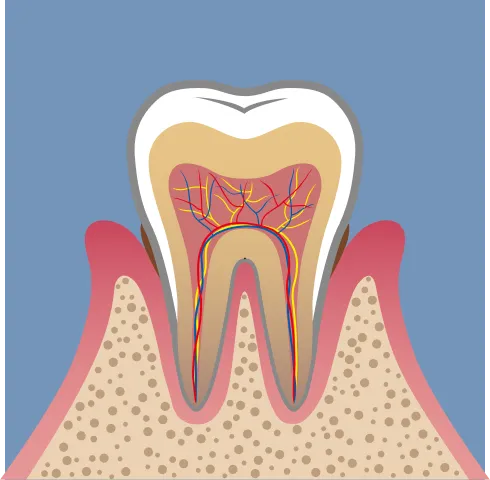

Step歯周病・重度歯周病の進行ステップ

健康な歯ぐき → 歯肉炎 → 軽度歯周炎

→ 中等度 → 重度へ

-

歯肉炎

軽度(歯肉炎〜軽度歯肉炎)

中等度(中等度歯周炎)

重度(重度歯周炎)

歯周病は、ある日突然悪化する病気ではありません。

健康な状態から少しずつ炎症が広がり、時間をかけて歯を支える骨や歯ぐきを蝕んでいく“慢性的な進行性疾患”です。初期段階では痛みがほとんどないため、気づかないうちに進行してしまうことが多く、「もっと早く治療しておけばよかった」と後悔する患者さんも少なくありません。

健康な歯ぐきは、薄いピンク色で引き締まり、ブラッシングしても出血しません。

しかし、歯と歯ぐきの境目にプラーク(歯垢)が蓄積し始めると、最初に「歯肉炎」が起こります。歯ぐきが赤く腫れ、歯みがき時に出血するなどの症状が見られるようになります。この段階であれば、正しい歯みがきと歯科医院でのクリーニングにより、健康な歯ぐきに戻すことが可能です。

放置すると、炎症は歯ぐきの奥深くに広がり、「軽度歯周炎」へ進行します。

歯を支える骨(歯槽骨)が少しずつ溶け始め、歯と歯ぐきの間に「歯周ポケット」と呼ばれるすき間ができるのが特徴です。このポケット内は酸素が少なく、歯周病菌が繁殖しやすい環境のため、炎症がさらに進行していきます。

「中等度歯周炎」になると、歯槽骨の破壊が進行し、歯のぐらつきが現れ始めます。噛むと痛い、膿が出る、口臭が強くなる、歯ぐきが下がって歯が長く見える――といった症状が増えていきます。この段階では通常のクリーニングでは改善が難しく、「歯周外科治療」などの外科的なアプローチが必要になるケースもあります。

そして「重度歯周炎」に進行すると、歯槽骨の大部分が溶け、歯が支えを失ってグラグラの状態に。

歯ぐきから膿が出たり、強い口臭を伴ったりすることも多く、最終的には歯が自然に抜け落ちてしまうこともあります。ここまで進行すると、失われた骨や歯周組織を再生させる「歯周組織再生療法」など、より高度な治療が必要となります。